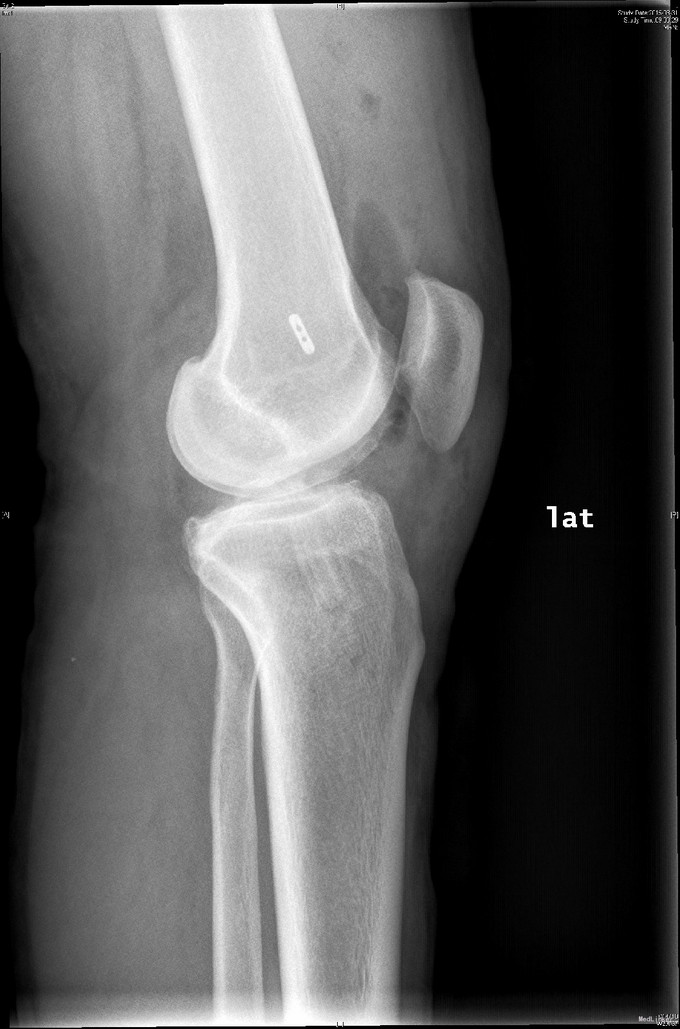

左膝扭伤后13年近1年反复不稳伴疼痛。 患者,男,39岁,13年前运动时扭伤左膝关节,当时未予重视,近1年出现左膝不稳伴疼痛,以上下楼、运动时明显,无法进行正常运动。遂于外院检查MRI(2015年3月)示:左膝关节退行性改变、左膝前交叉韧带信号异常、半月板信号异常、左膝关节内积液。为求进一步诊治来我门诊就诊,结合病史及体征,诊断“左膝半月板损伤、左膝前交叉韧带损伤”并收入院行进一步治疗。

右下肢、双上肢肌力及活动度正常。左股四头肌轻萎缩,肌力V-级。膝关节(无明显)肿胀,膝关节ROM受限:伸/屈:20度/110度,关节过伸过屈时无疼痛。髌骨活动度正常,髌周无压痛。浮髌试验(-),压、磨髌(+)。麦氏征(+),外侧关节间隙疼痛(+)。ADT(+),Lachman征(+),轴移试验(+),侧方应力试验(-)。双下肢无明显感觉异常。

入院诊断:左膝半月板损伤、左膝前交叉韧带损伤 治疗:入院后行左膝关节镜下外侧半月板成形+髁间窝成形+前交叉韧带自体肌腱重建手术。